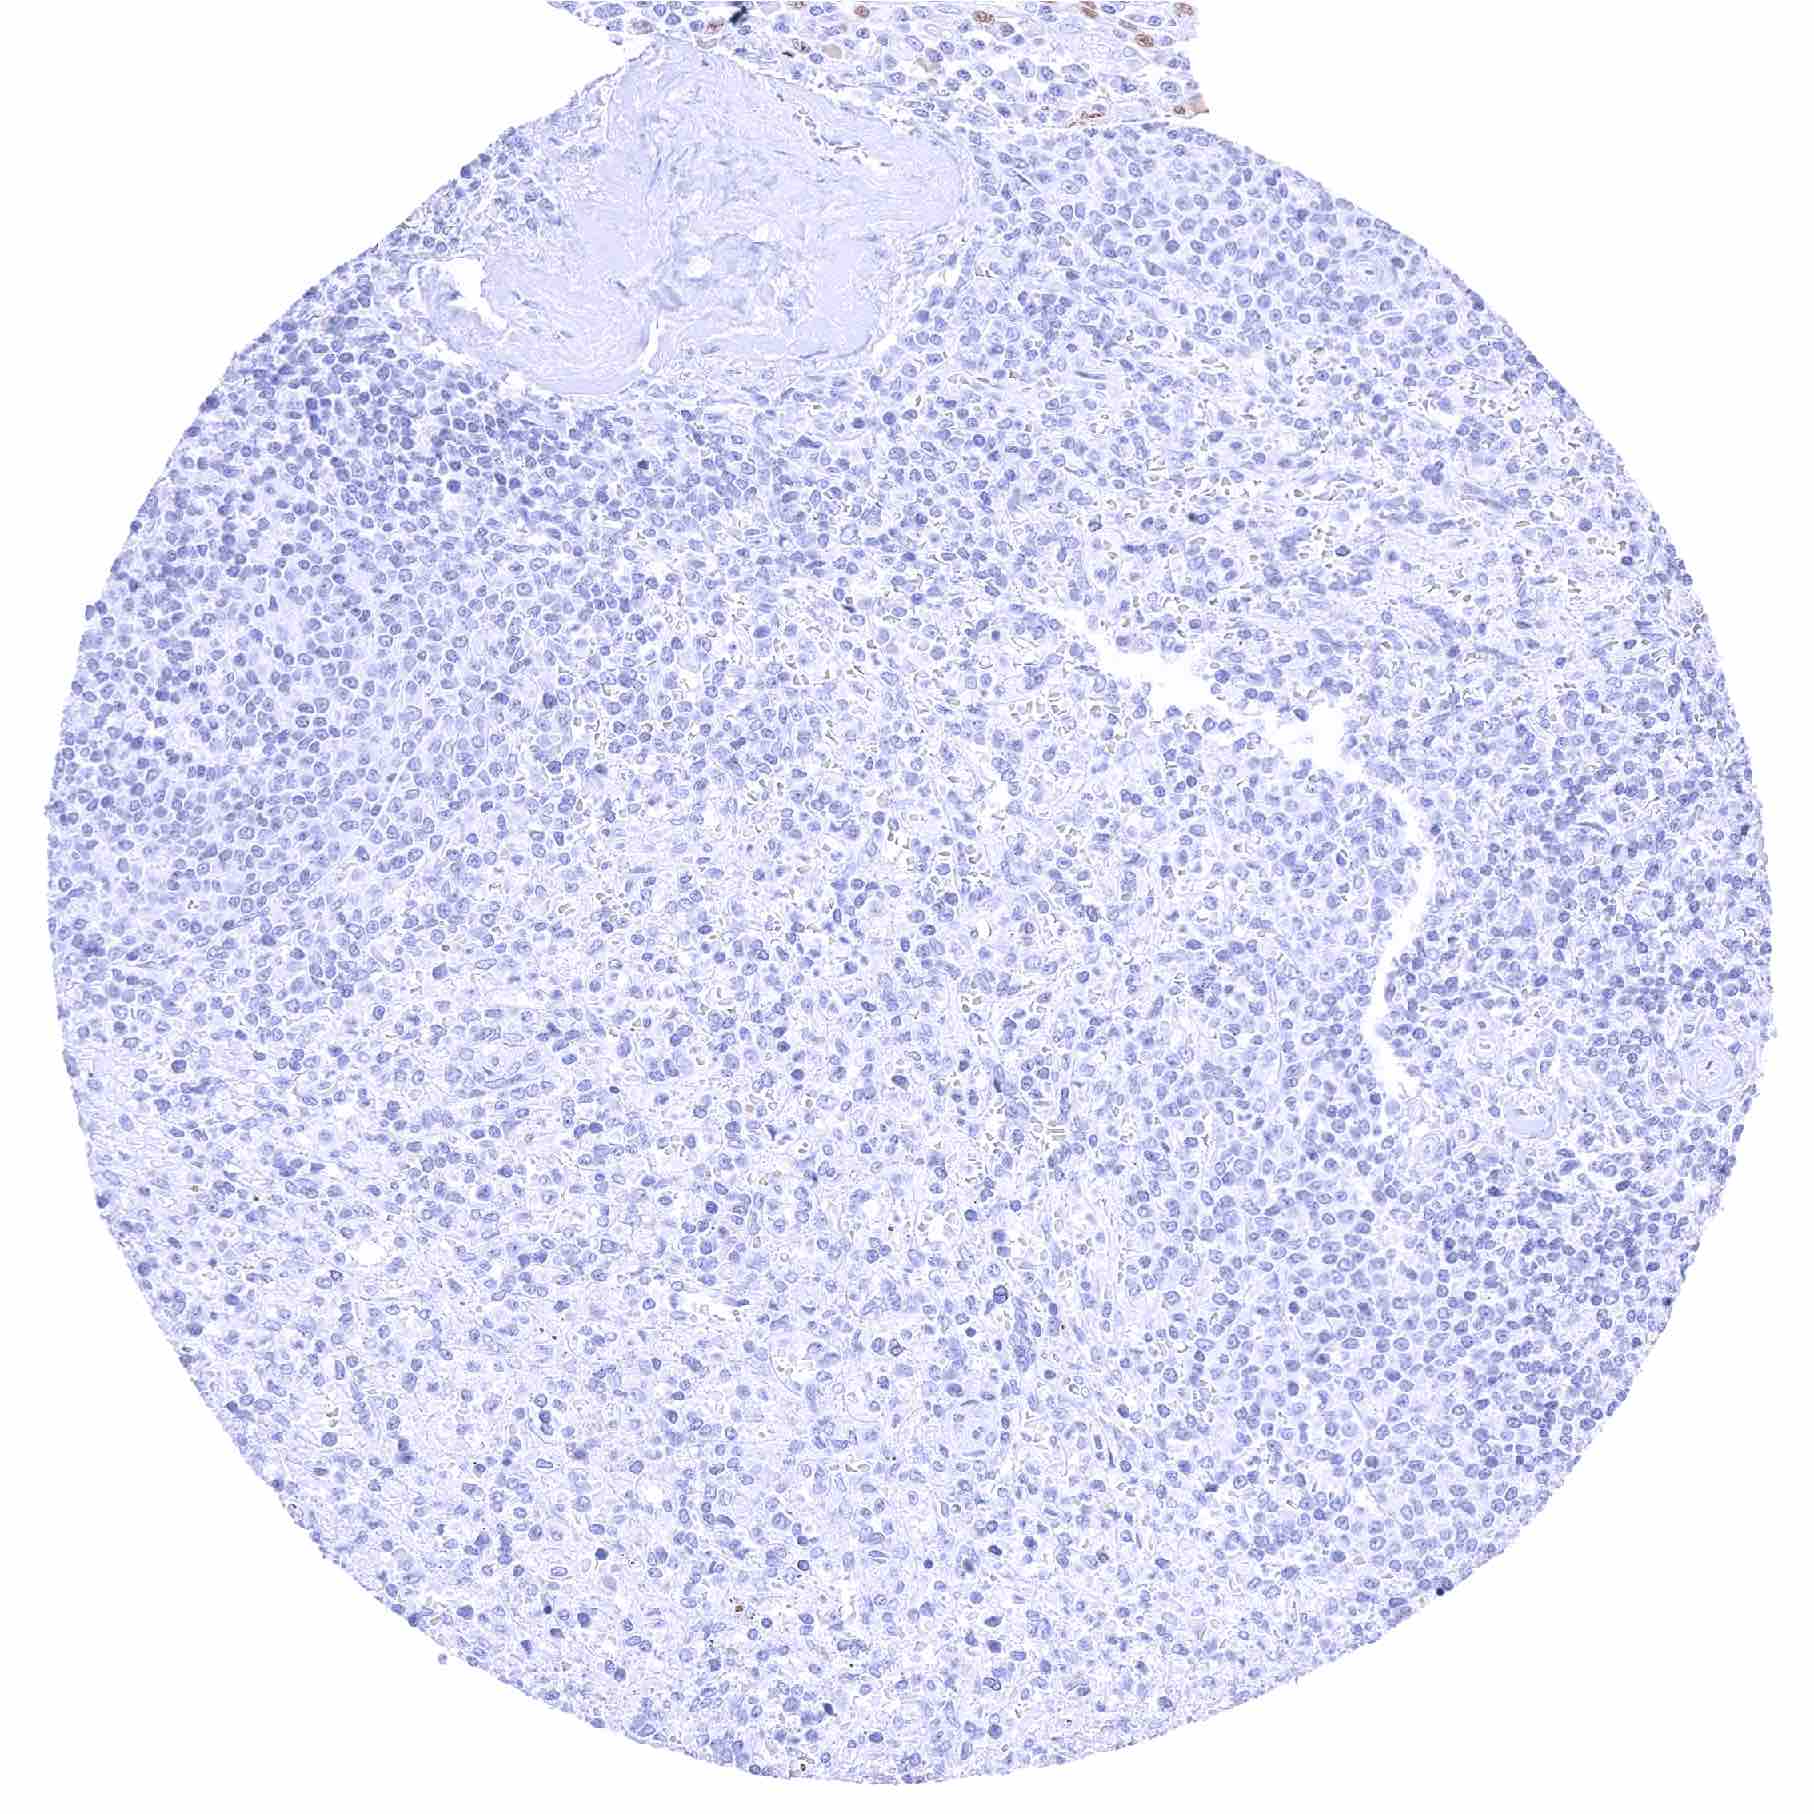

Spleen.jpeg